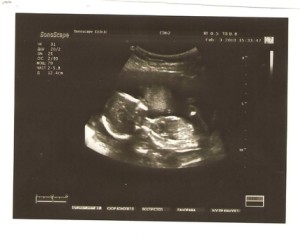

Знімки УЗД на 17 тижні вагітності

Знімки 3D УЗД на 17 тижні вагітності